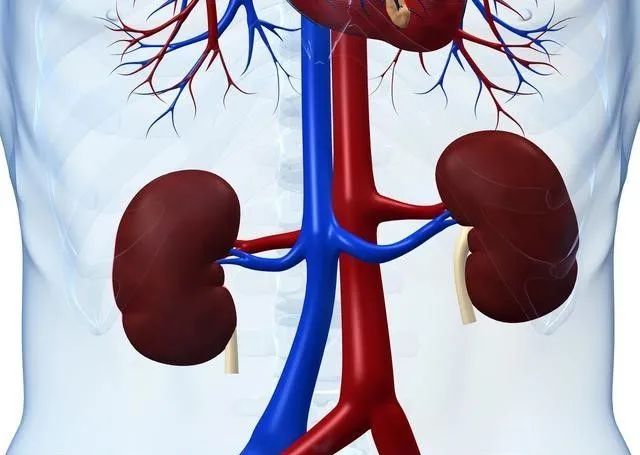

患者一個月前感覺右腰部脹痛,隨后出現(xiàn)雙下肢水腫,遂至當(dāng)?shù)蒯t(yī)院就診,檢查結(jié)果提示:右腎腫瘤并侵犯下腔靜脈,無法完成超高難度手術(shù),建議轉(zhuǎn)上級醫(yī)院治療。

轉(zhuǎn)至中南大學(xué)湘雅二醫(yī)院就診,急診科張東山教授聯(lián)合泌尿外科張磊副教授會診并為患者進(jìn)一步檢查,發(fā)現(xiàn)患者肝臟、腹膜后淋巴結(jié)、肝右靜脈及下腔靜脈都被侵犯并轉(zhuǎn)移。

患者右側(cè)肝腎間隙巨大腫塊及肝臟轉(zhuǎn)移灶緊臨右肝靜脈、壓迫下腔兩大主要靜脈及膽管,且兩大靜脈已被腫瘤侵犯,術(shù)中稍加不小心,隨時會造成大出血。右腎、右輸尿管受壓、積水,腹腔內(nèi)失去正常的解剖結(jié)構(gòu),加上患者既往有甲亢病史及高泌乳素血癥,對手術(shù)操作、麻醉及術(shù)后管理均提出了極大的挑戰(zhàn)。